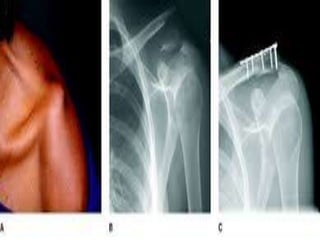

 Fracture by falling on the outstreched hand

 Common site of fracture is junction between

the two curvature of the bone (weakest point)

 Lateral fragment is displaced downward by

the weight of limbs